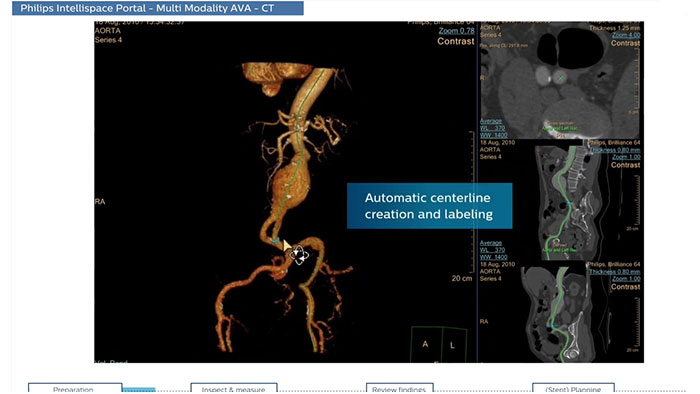

CT Advanced Vessel Analysis (AVA) Stent Planning includes multiple preset and user-defined options to gain detailed information for use in stent planning.

Comprehensive vascular analysis planning

Designed to examine and quantify different types of vascular lesions from CTA and MRA scans. It accommodates different modes of inspection, allows labeling different vascular lesions, and helps navigating through multiple findings. Demonstrated to reduce the post-processing time by 50% when compared to manual Head & Neck CT angiography (CTA) analysis*.